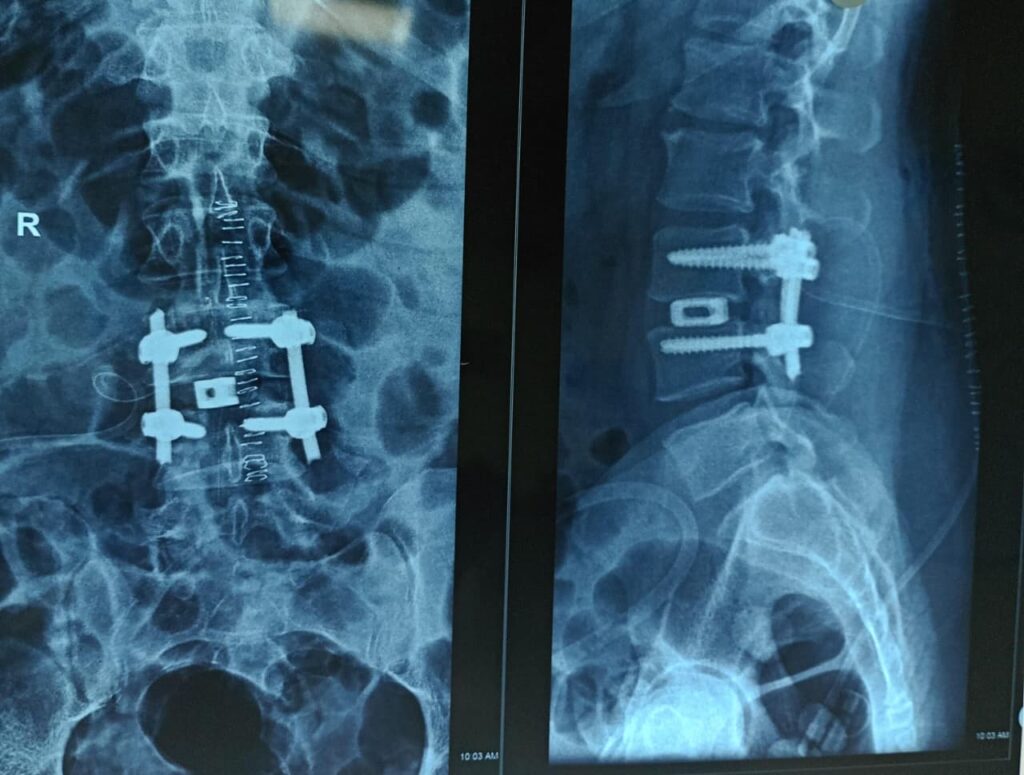

Complex Trauma & Fracture Management

- Open & Complex Fracture Fixation

- Non-union & Malunion Correction